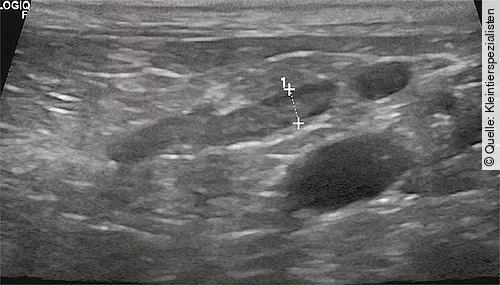

Die Ultraschalluntersuchung des Abdomens dient zum einen der Beurteilung der Nebennieren, aber auch zum Ausschluss anderer Differenzialdiagnosen. Bilateral kleine Nebennieren sind hinweisend für einen Hypoadrenokortizismus.

Ein Durchmesser des kaudalen Pols der linken Nebenniere von < 3,2 mm gilt als hinweisend [29]. Normal große Nebennieren schließen einen primären Hypoadrenokortizismus nicht aus. Bilateral vergrößerte Nebennieren können ein Hinweis auf eine neoplastische oder inflammatorische Genese sein.